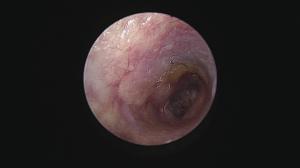

繰り返す外耳炎で意外と知られていない原因に「ゴミの蓄積」があります。

ゴミと言っても成分は細菌、脂、汗、毛、炎症細胞・・などなどが混じって形成されています。

そのゴミが鼓膜付近に蓄積していると、点耳薬や洗浄(一般的は)は効果を十分に発揮できません。

まずはこの汚れをしっかり除去することが重要ですね。

この除去はやはり大変です・・鼓膜があるのと、耳の道が狭いこと(晴れている場合も多い)、動くのでそもそも無理・・

道内では珍しい耳道内視鏡治療を積極的に行っています(麻酔下で初めに除去することでその後のケアが楽になるので他施設で行っていない施術を当院では取り入れています)

これがなかなか技術が必要ですが、処置後の経過が良いことがモチベーションになります!

この耳道内視鏡はあまり知られていませんが、お困りの症状にあった処置ができますので今後もアナウンスしていきます!